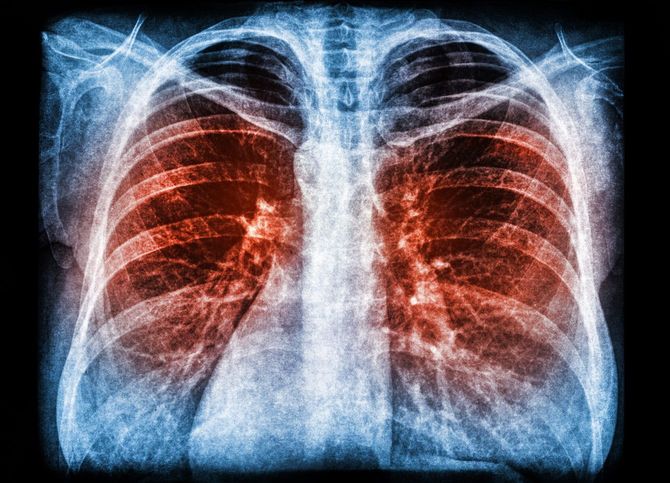

2019年10月初旬。父親は突然体調を崩し、施設から病院を受診。点滴などの処置をしてもらったが、その後は食事も摂らずに横になっていた。何度か職員が様子を見に巡回していたが、深夜に呼吸が止まっていることに気づき、病院へ救急搬送されたが、死亡が確認された。78歳だった。

「深夜に連絡をもらい、急いで施設に到着すると、父の身体はまだほんのり温かく、顔は微笑んでいるように穏やかでした。死因は肺炎の疑いとなっていましたが、眠るように静かに亡くなったようです」

肺炎のX線画像

写真=iStock.com/da-kuk

※写真はイメージです